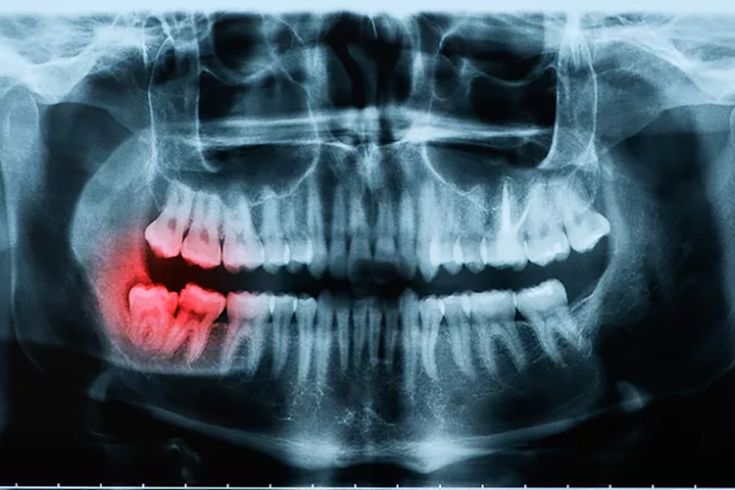

Chụp X-quang vùng hàm: Bệnh nhân được chỉ định chụp X-quang răng và xương hàm để phát hiện tổn thương sâu, tiêu xương hoặc viêm không thể quan sát bằng mắt thường.